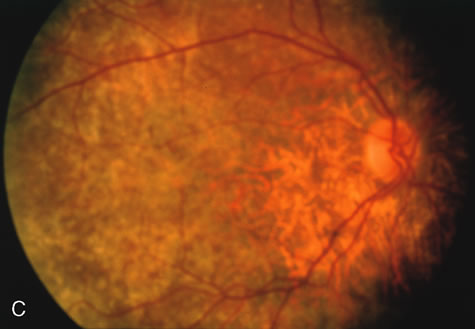

Of more clinical importance is the role of FA in the diagnosis and treatment of cystoid macular edema (CME) (Fig. 1C and D). Stereoscopic FA indicates that the leakage, which may be diffuse or have the typical petaloid stellate appearance of CME, can come from the perifoveal retinal capillaries, from the choroid through the RPE, or from a combination of both sources.4 With the recent suggestion that CME in RP may be successfully treated with acetazolamide,5, 6 FA is thus important to document the diagnosis of CME, establish the origin(s) of leakage, and follow patients during and after therapy.